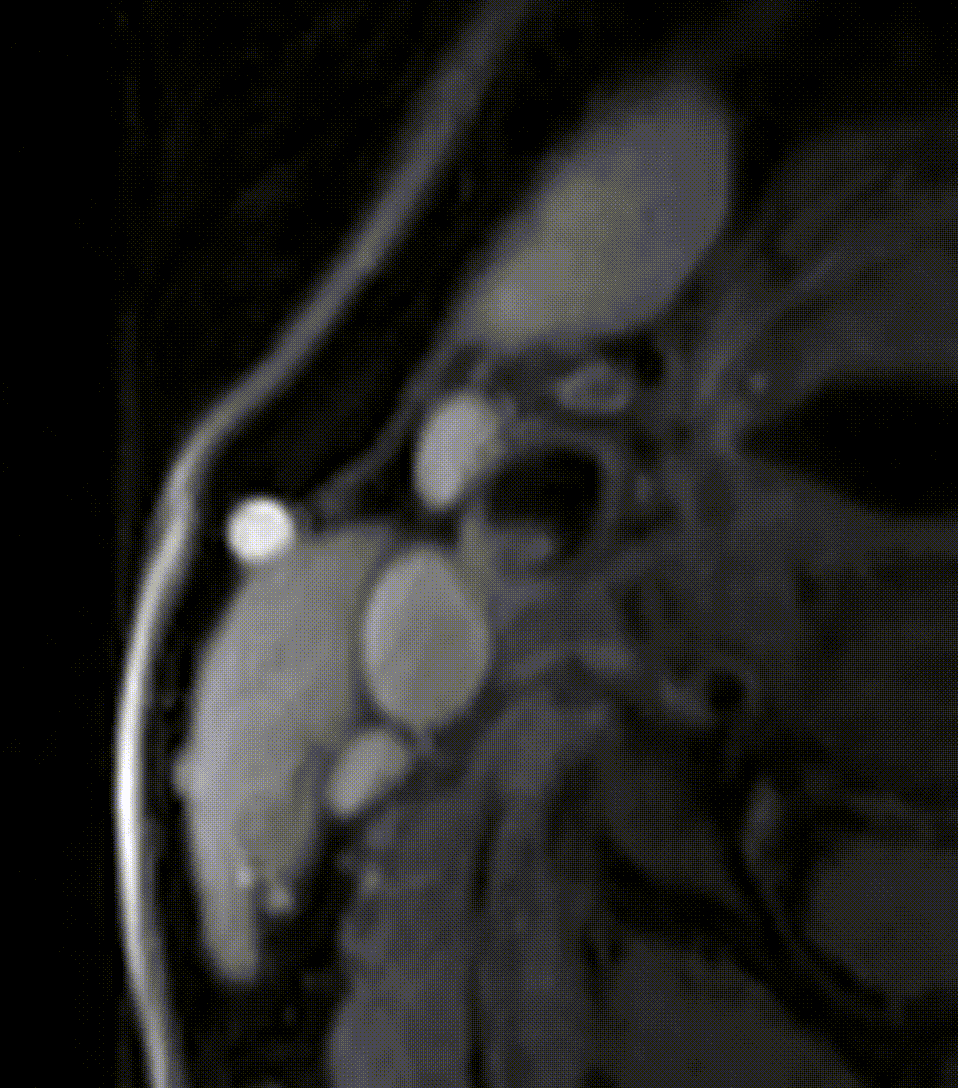

Carotid Artery Imaging

We are interested in understand morphology, wall/plaque composition and wall dynamics of the carotid artery and how these alter in carotid artery disease. This research activity consists of three connected projects:

- Development of new dynamic fast-spin echo imaging approaches (using non-linear sampling, parallel imaging and compressed sensing) for time-resolved imaging of carotid arteries (see movie)

- Characterization of wall distensibiity, morphology and plaque composition with age and disease, and exploration of impact on stroke and neurodegenerative disorders. Includes application of deep learning based segmentation and analysis approaches.